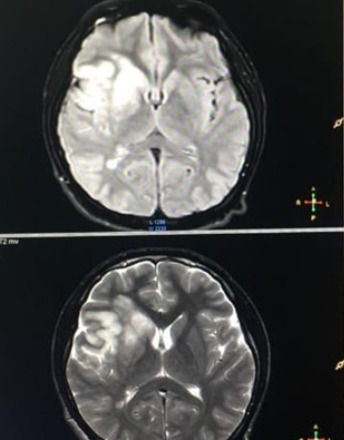

Study on Imaging Findings, Pathology and Treatment of Cerebellar Infarction

To explore the pathological mechanism and clinical treatment of cerebellar infarction through the clinical imaging changes of cerebellar infarction.